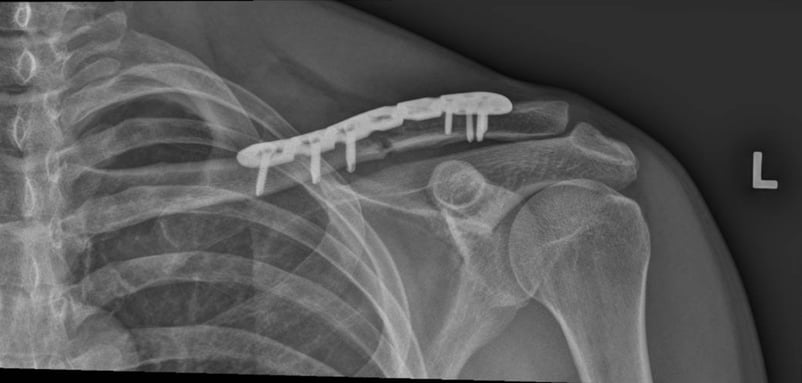

Internal Fixation: This involves using screws, plates, or pins to hold the bones together. The surgeon will make a small incision and carefully position the hardware to stabilise the bone.

Post-Surgery Care: After surgery, you may need to wear a sling for several weeks, and the doctor may schedule follow-up visits to monitor the healing process.

Good healing of a fracture after surgical fixation with a plate and screws.